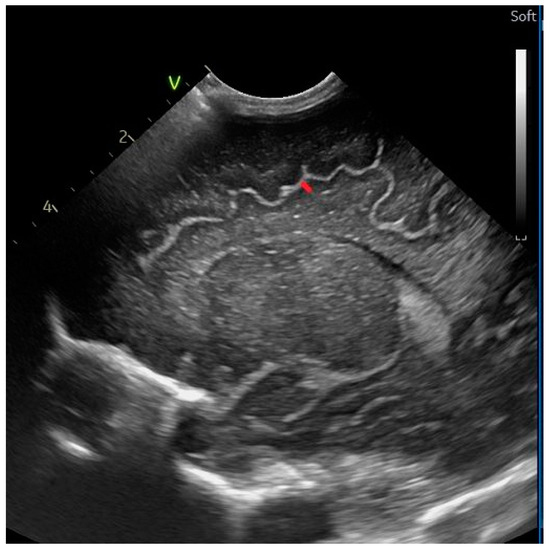

2.2. Head Ultrasound Measurements at TEA